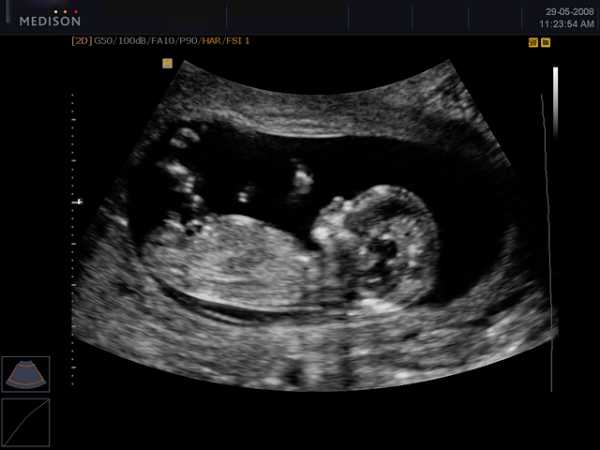

Фото:

На этом сроке УЗИ уже показывает четкие контуры будущего ребенка, можно отчетливо наблюдать его маленькие ручки и ножки.

К 12 неделе вес будущих мальчиков и девочек увеличивается практически в два раза. В среднем этот показатель для плода в этот период составляет порядка 15 грамм, рост достигает 10 сантиметров.

На УЗИ в этот период можно рассмотреть небольшие ручки и ножки маленького человечка. Если вглядеться в личико ребенка, то на нем уже будут заметны глаза с веками, а также сформированные нос и рот. На руках малыша уже заметны первые ногти.

Фото УЗИ на 12 неделе беременности

Изучать развитие плода можно рассматривая УЗИ по неделям беременности.